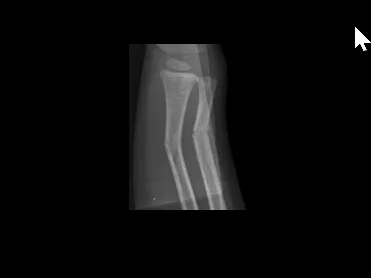

- Typical pediatric fractures

- Non accidental trauma